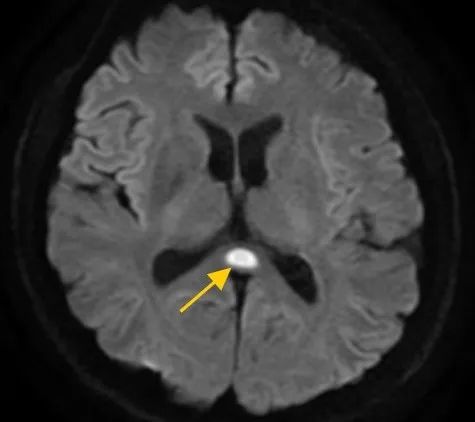

于是他马上到医院就诊,并被转入神经内科。经过一系列检查后,医生诊断为:可逆性胼胝体压部综合征。

什么是“可逆性胼胝体压部综合征”?医生解释,如果把大脑比作一座城市,胼胝体就是连接左右脑的“跨海大桥”,而胼胝体压部正是桥上的“核心枢纽”。当它因酒精、熬夜或感染“肿了”,大脑信号就会“堵车”,引发一系列“故障”。

董先生大脑的影像结果显示,胼胝体压部发生病变

所以,董先生才会出现视物模糊、看不清东西等问题。除了“压部”,胼胝体的其他部位也有病变,所以小董才会出现幻听、手抖等症状。如果简单来说,那就是把“脑子喝坏掉了”。①